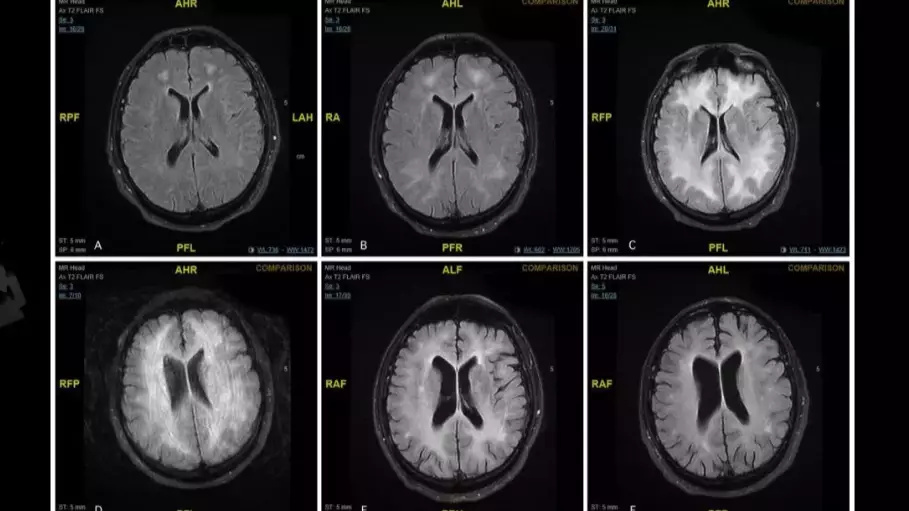

Images have been released that show the effects of cocaine on the human brain and the damage that the Class A substance can do in a very short amount of time.

The brain scans show how cocaine can 'eat away' at the brain, sometimes leaving the user with disabilities and - in extreme cases - dead.

The patient from whom the scans were taken was suffering from a rare but severe side-effect of cocaine use called cocaine-induced toxic leucoencephalopathy.

The white matter in his brain was discovered to have been damaged, which led to their diagnosis.

Four months later, his recovery was so successful that he was allowed home. In the intervening year, he has stayed clear of drugs and his yearly follow-up showed that while there were still 'persistent white matter changes' in his brain, neurological tests were normal.